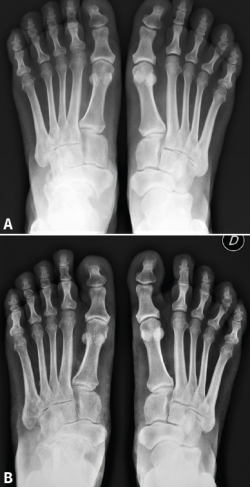

Resultados: todos los pacientes tenían un varo subtalar y el 88,2% una fórmula metatarsal index minus. Existió una mejoría en todas las escalas de valoración utilizadas y en los parámetros radiológicos estudiados (cobertura talonavicular y clasificación de Maceira) en la mayoría de los pacientes. No se registraron complicaciones importantes. Un paciente no mejoró y precisó de una artrodesis a los 4 años de la osteotomía.

Conclusiones: la EMW produce un pie plano paradójico. La corrección quirúrgica del varo subtalar permite una mejoría clínica y radiológica notable. La osteotomía “supervalguizante” es una técnica sencilla y se ha constituido en nuestra técnica de elección, independientemente del estadio radiológico. La artrodesis de la columna medial ha quedado como técnica de rescate para fracasos de la cirugía de preservación articular.

Results: all patients presented with subtalar varus and 88.2% had a metatarsal index minus formula. There was an improvement in all scales studied. Radiographic parameters also improved in all cases (talonavicular coverage, Maceira classification). Most patients had considerable pain relief and just one did not improve and required an arthrodesis four years after the osteotomy.

Conclusion: MWD presents with a paradoxical flatfoot varus. Surgical correction of hindfoot varus allows for a mechanical change that produces clinical and radiological improvement. An isolated “super-lateral-slide osteotomy” is an easy technique to achieve varus correction regardless the radiographic stage of the disease and has become our surgical procedure of choice. Medial column arthrodesis is left as a salvage procedure for those cases that do not improve with the osteotomy.